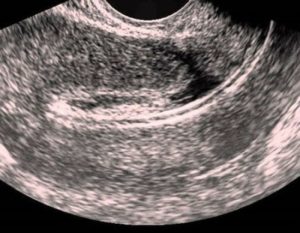

Трансвагинальное УЗИ

Визуализация рубца после кесарева сечения при проведении трансвагинального УЗИ